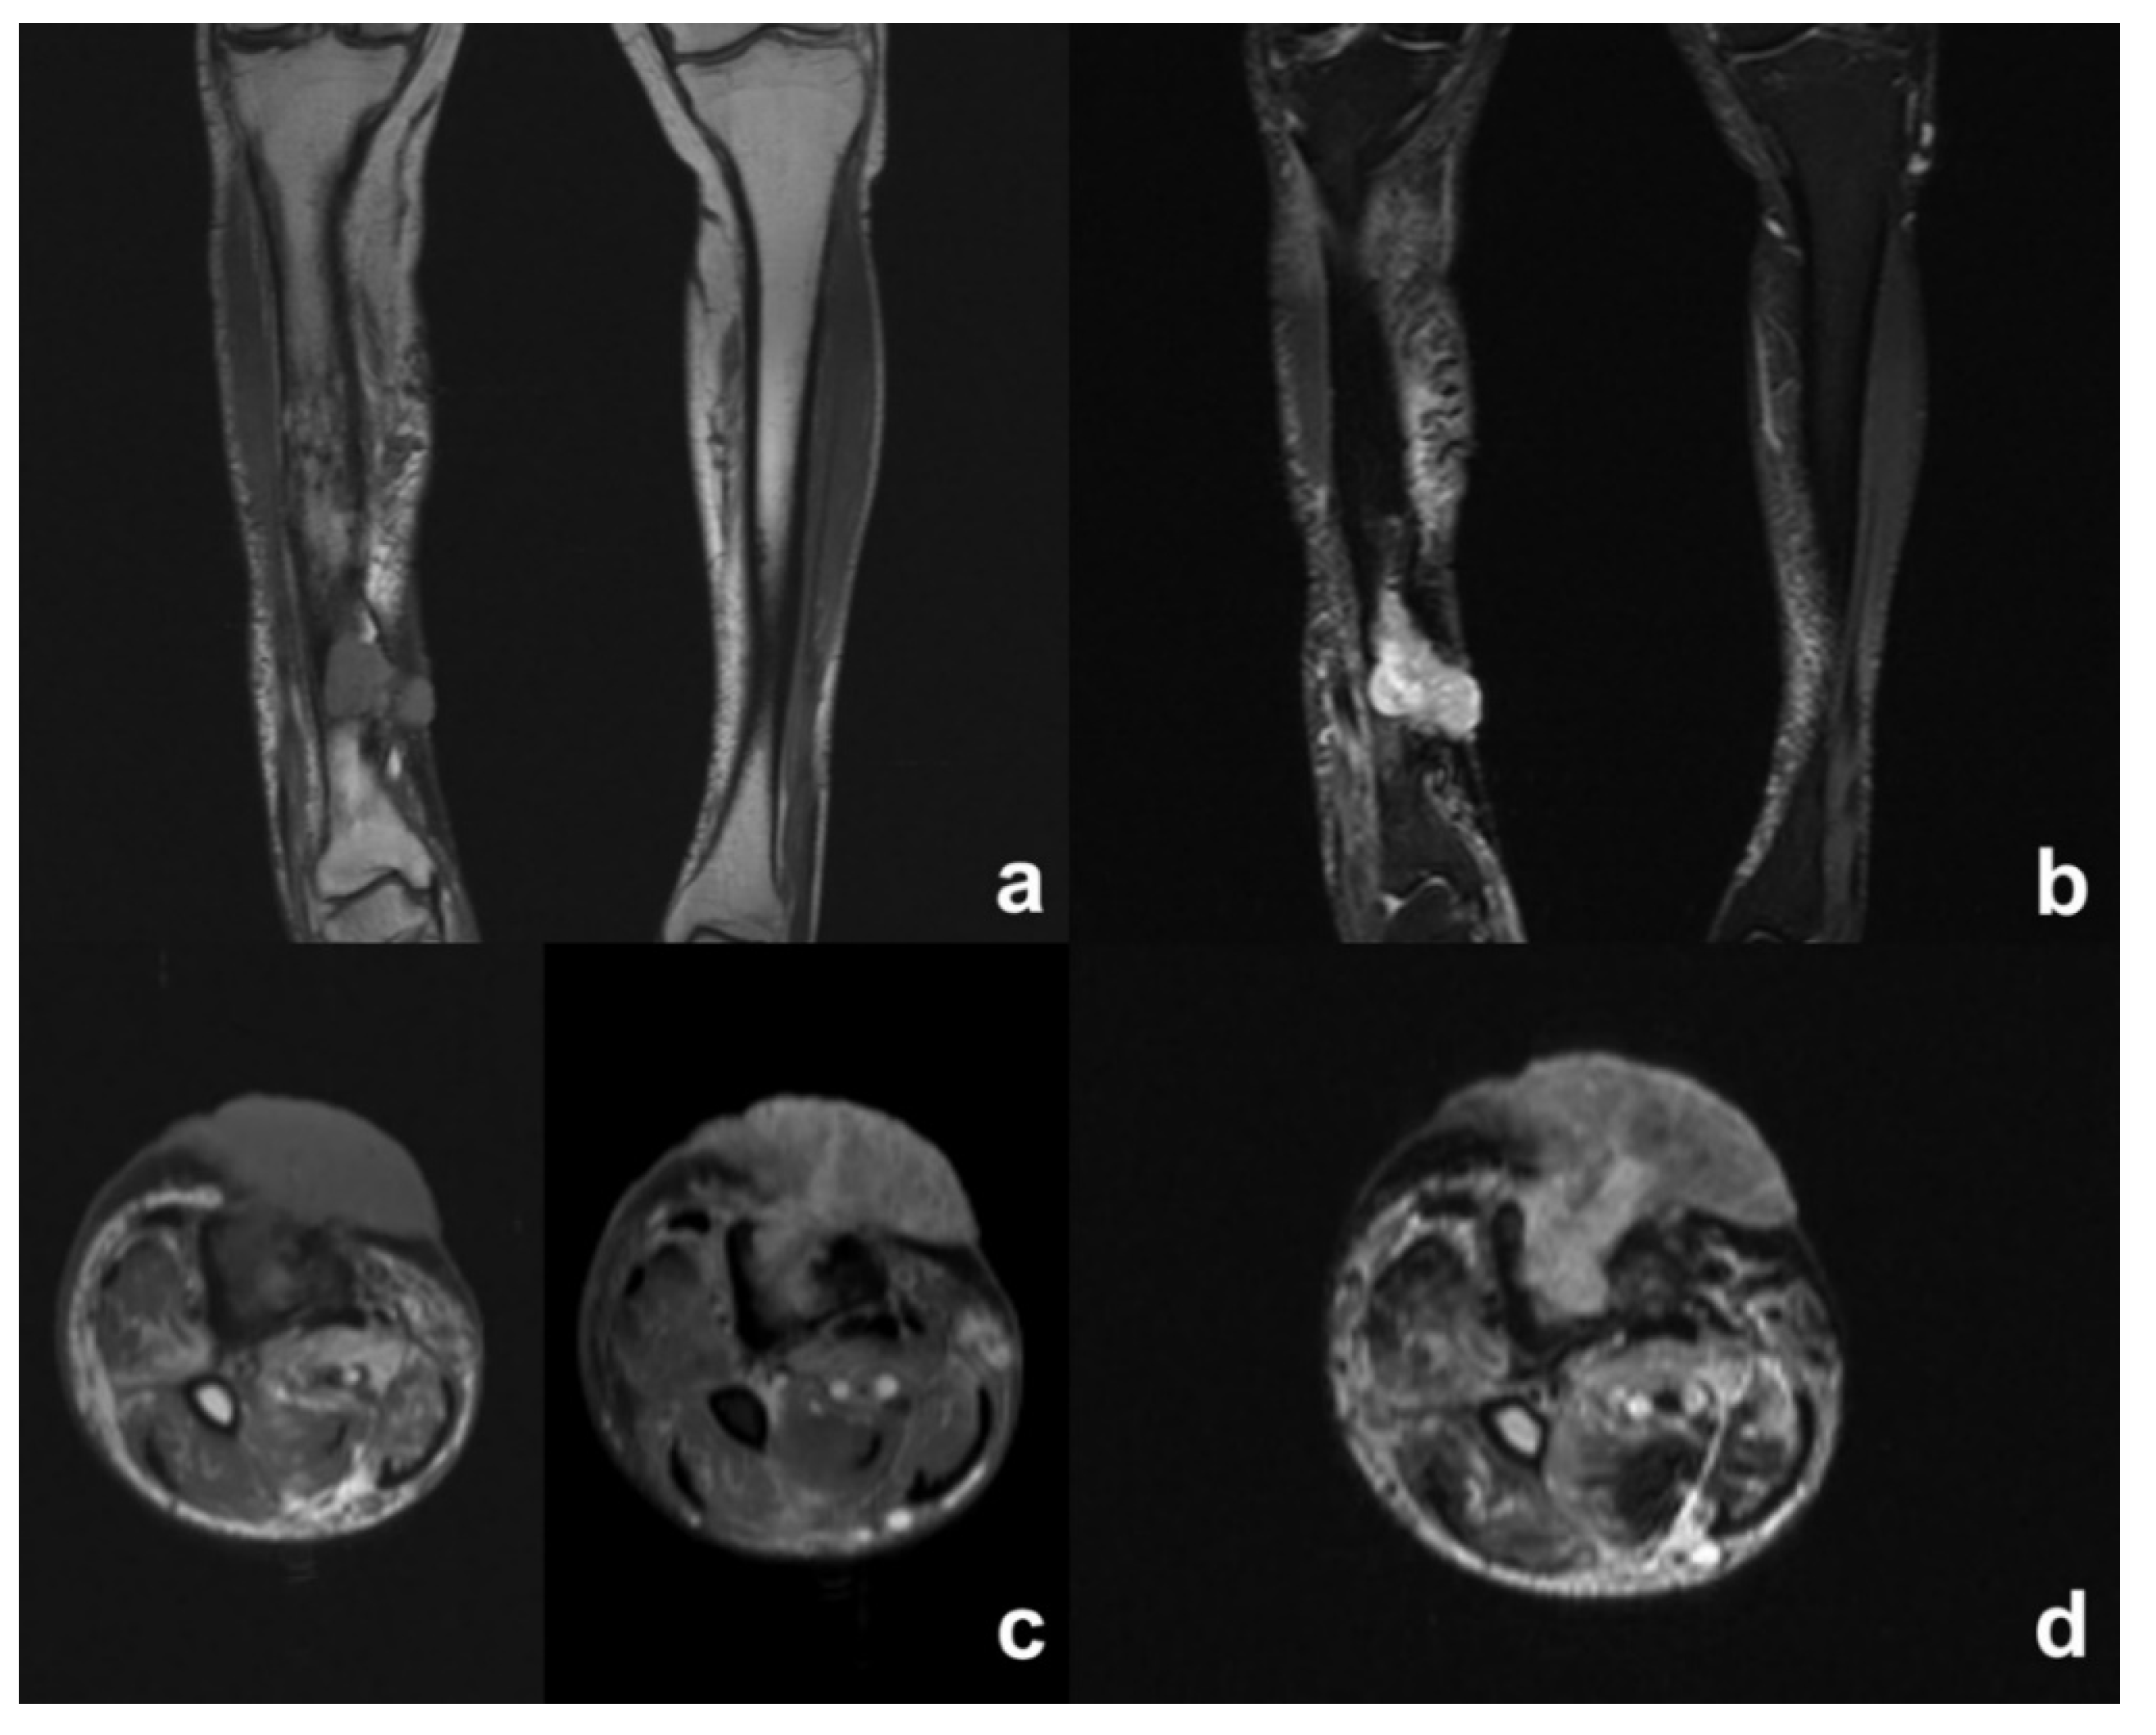

| MRI Signal | Diagnosis | |||||

|---|---|---|---|---|---|---|

| T1 | Stir | T1 MoC | AO | CO | SCC | |

| Bone Marrow Edema | Low | High | High (Increased) | Common | Less common # | =CO |

| Intraosseous abscess | Low | High | Peripheral Enhancement | Uncommon | Uncommon # | =CO |

| Cortical bone | Low | Low | No Enhancement | Normal or Periosteal Elevation | Thickened, extensive remodeling | =CO |

| Sinus tract | Low | High | Peripheral Enhancement | Never | Very common | Always |

| Sequestrum | Low | Low | Peripheral Enhancement | Never | Less Common | =CO |

| Extraosseous soft tissue changes | Low | High | Enhancement | Very common | Less Common * | Mass developing in the epithelial tract of the fistula |